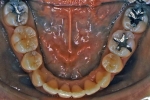

| 治療後3年経過時

|